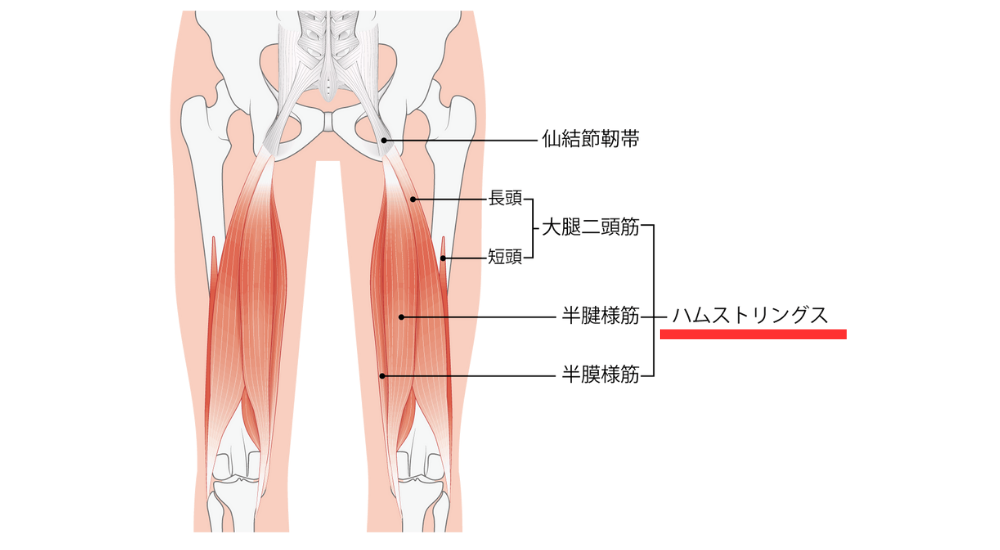

- ハムストリングス:

太ももの裏側の筋肉。大腿四頭筋と拮抗関係にあり、骨盤の傾きに関与します。硬く、弱くなると反り腰になり、腰に負担をかけます。